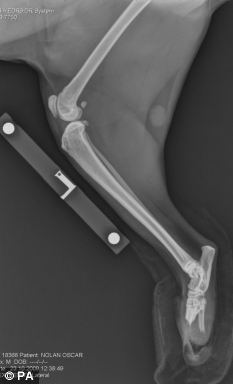

手術前貓腿X光照片

接受手術的這只貓叫奧斯卡,今年2歲,9個月前,在一次事故中它的兩只后爪被聯合收割機切斷,險些喪生。正常情況下,3條腿的貓還能正常生活,但2條腿的貓就不行了。

菲茨帕特里克醫生說:“我們只能給它裝新腿,否則只能實施安樂死。但還沒人做過這樣的手術。”醫療團隊研究了鹿角如何生長,根據這個原理,他們把兩個特制的含鈦及其它成分的金屬棒,釘入奧斯卡的后腿。然后在金屬棒的末端安上仿生爪子。不過,奧斯卡以后只能在室內活動,因為這種假肢不合適戶外的環境。